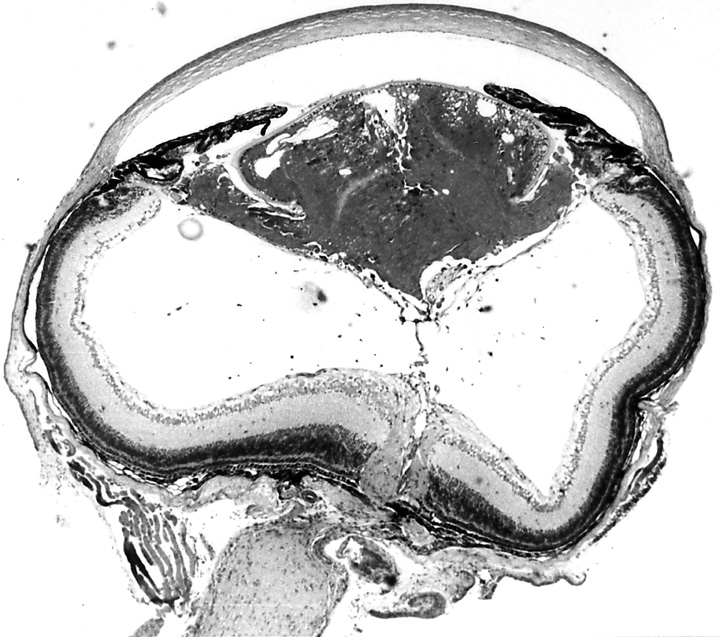

Figure 1a. Eye of To3/To3 homozygote, age 18 days.

The lens is vacuolated, and the lens capsule has ruptured.

The vitreous chamber is abnormally small.